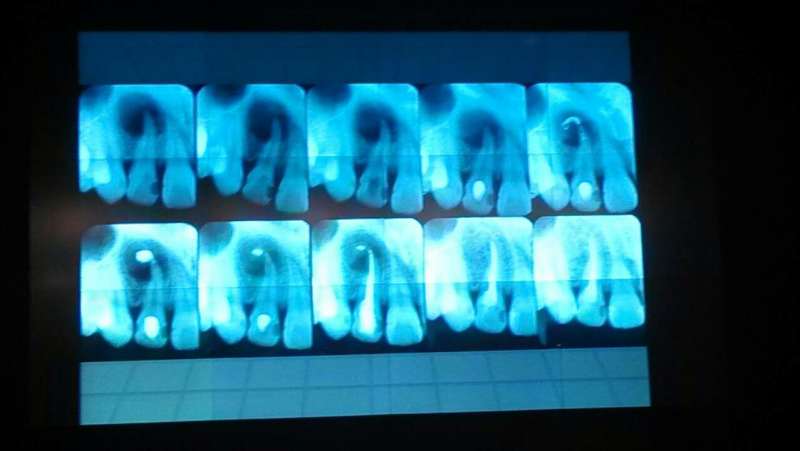

趙幫樹病例

來源于江思玉2群收集整理